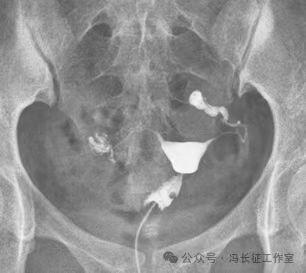

微信图片_20240223171216(3).jpg

栓塞后造影显示弹簧圈固定在双侧输卵管间质部和峡部近段,造影剂未能通过栓塞段,说明输卵管管腔被完全封闭。